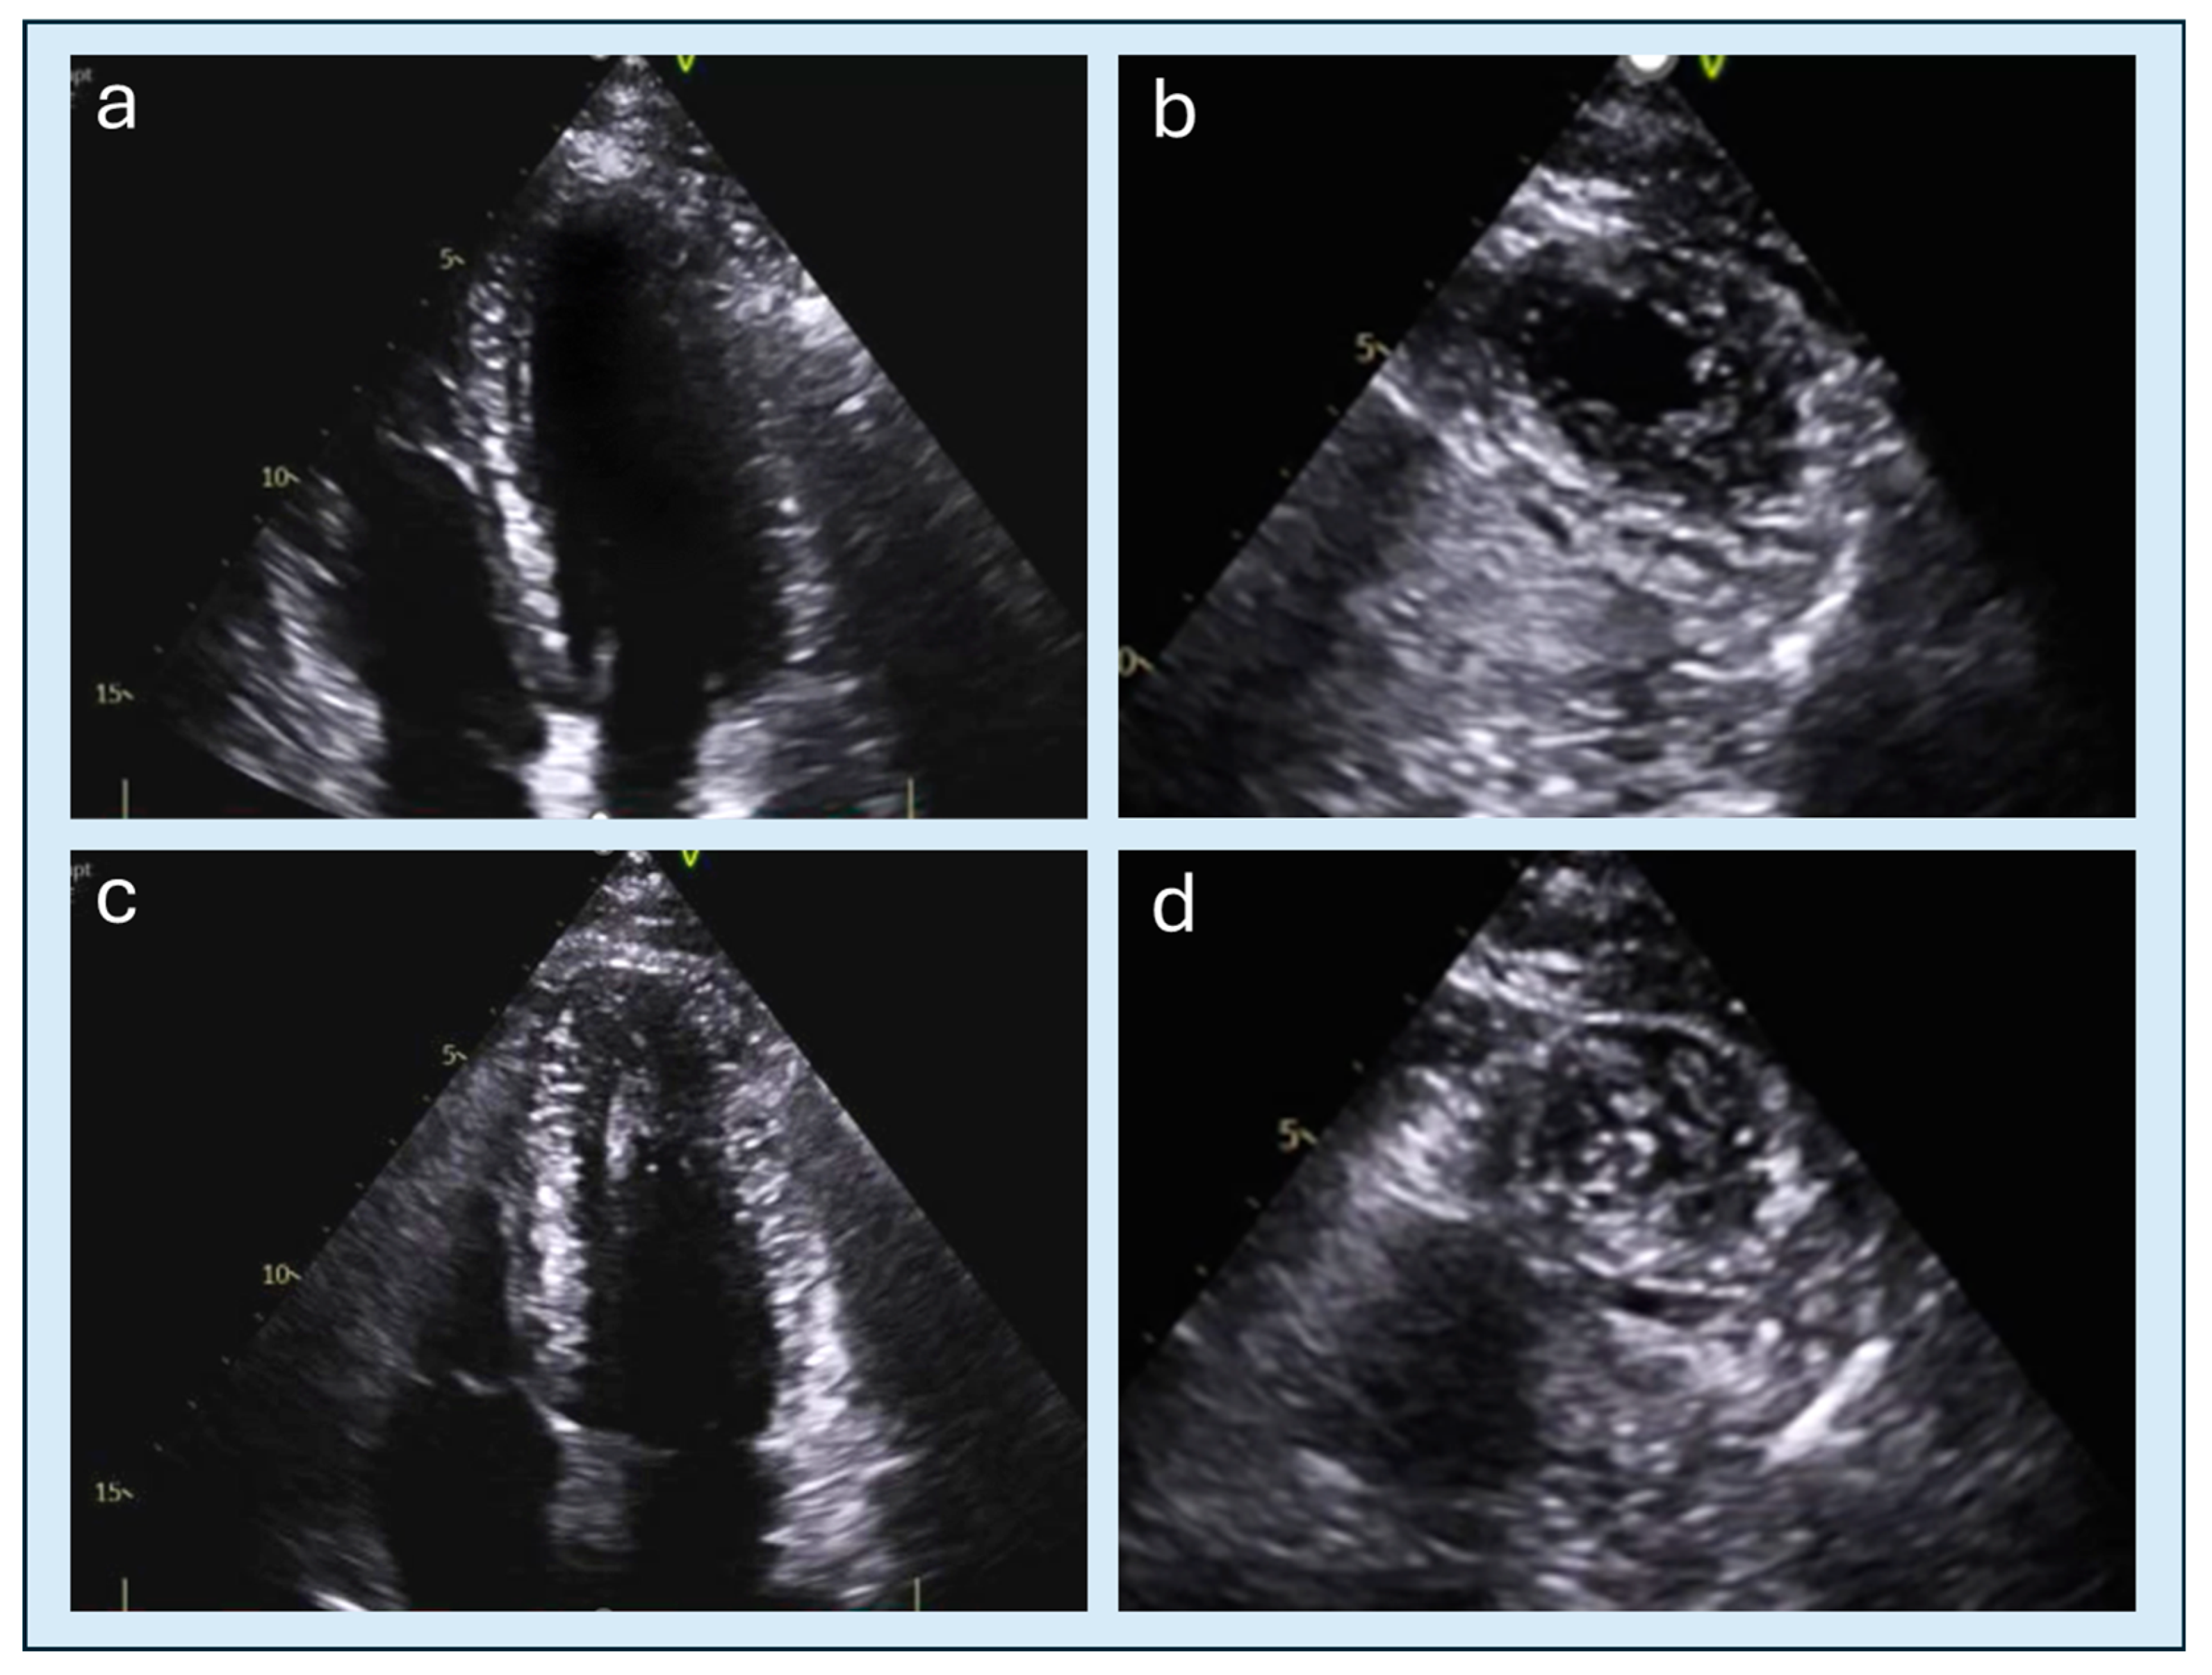

4. Echocardiography

4.2. Apical Obliteration